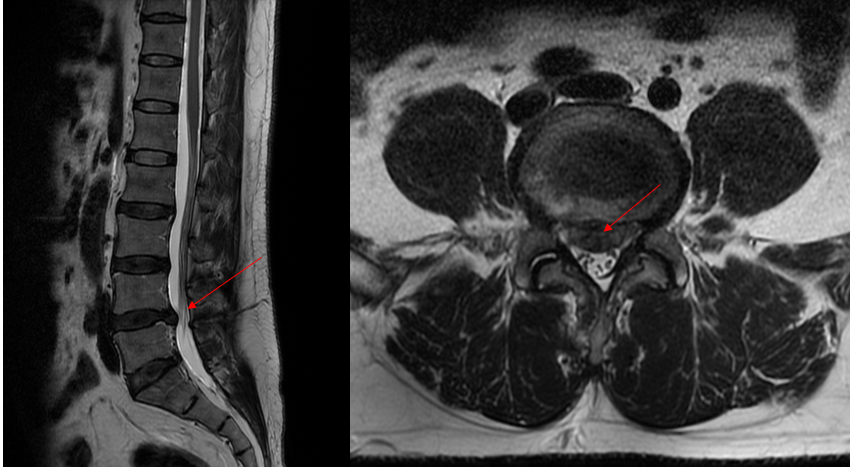

罪魁祸首--突出的椎间盘

经过充分和精心的术前准备,姜为民主任医师团队成功为患者施行“内镜下腰椎间盘融合术+经皮椎弓根钉内固定术”,术中借用O臂机和手术机器人,通过先进的影像引导系统,对患者的脊柱进行准确的三维重建和规划。手术医生在计算机屏幕上看到患者的脊柱结构,并根据个体化的解剖特征进行术前计划,为手术提供了更准确的定位和手术路径规划,将误差控制在1mm以内。此次手术过程仅1.5小时,术中出血量不足50ml,伤口为两个1cm切口,符合当前微创及快速康复理念。术后第3天,患者可以下床活动,对术后疗效非常满意。